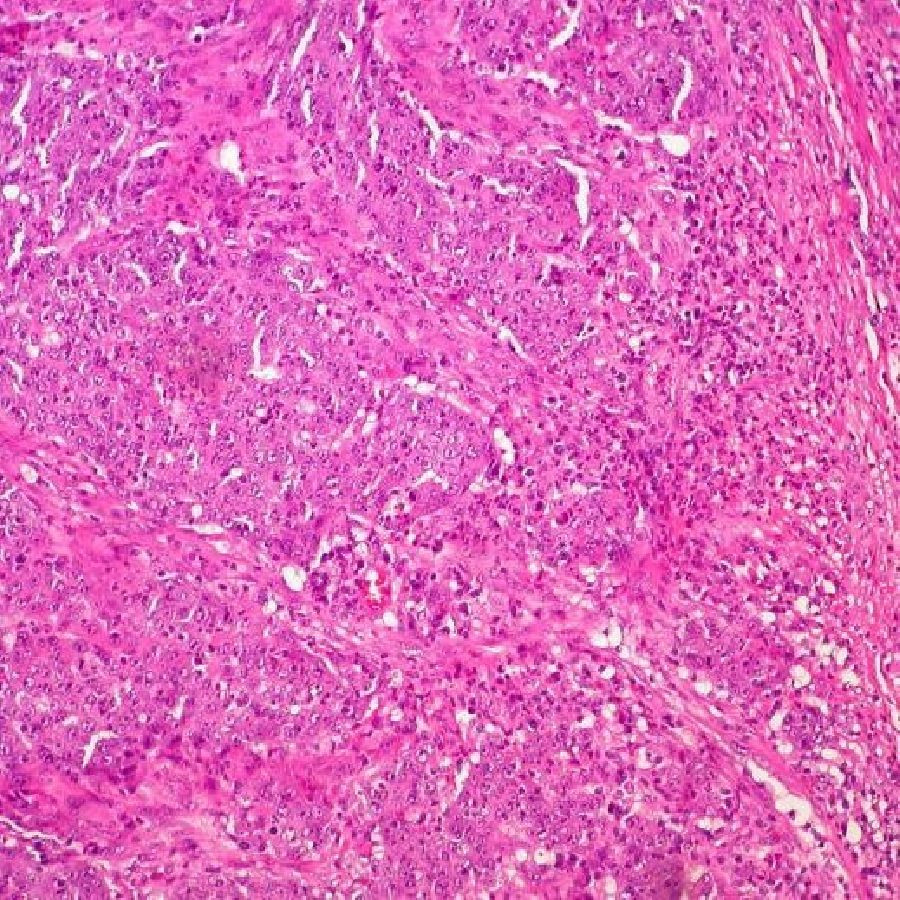

La inmunoterapia puede ser eficaz para pacientes con cáncer colorrectal metastásico no diseminado al hígado

Los investigadores de City of Hope, un centro de investigación y tratamiento de cáncer, diabetes y otras enfermedades mortales en Estados Unidos, analizaron el tipo más común de cáncer colorrectal metastásico y han descubierto que estos pacientes responden mejor a la inmunoterapia de bloqueo de puntos de control, un tratamiento innovador que ayuda al sistema inmunitario a reconocer y atacar las células cancerosas, si los tumores no se han extendido al hígado.

Estos resultados, publicados en la revista 'JAMA Network Open', son importantes porque la inmunoterapia se ha considerado tradicionalmente ineficaz contra el cáncer colorrectal estable por microsatélites (MSS), que representa el 95% de todos los casos de cáncer colorrectal metastásico. Estos pacientes tienen pocas opciones de tratamiento una vez que se vuelven resistentes a la quimioterapia.